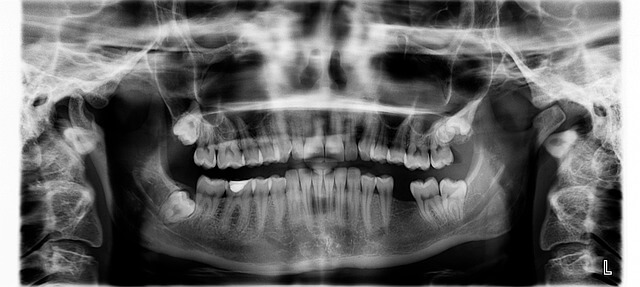

1. 크라운 치료란 무엇일까?

*많은 사람들이 처음 듣는 순간 낯설게 느끼지만, 크라운 치료는 생각보다 단순한 개념입니다. *쉽게 말하면 약해진 치아를 튼튼한 뚜껑으로 덮어주는 과정이에요. *제가 직접 경험해 보니, 깨진 치아 때문에 음식조차 씹기 힘들었는데 크라운 치료 이후로는 딱딱한 음식도 편하게 먹을 수 있었습니다. *실제로 주변에서도 크라운 치료로 다시 자신 있게 웃게 된 사례를 많이 봤습니다. *당신도 치아가 쉽게 깨지거나 색이 변해 불편하다면, 크라운 치료가 가장 빠른 해결책이 될 수 있습니다.

- 치아가 많이 닳았을 때

- 충치로 인해 약해졌을 때

- 치아 색이나 모양 개선이 필요할 때